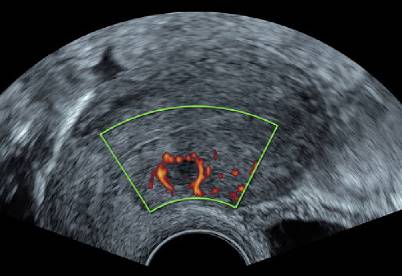

Abb. 11

Im Farbdoppler können Adenomyoseherde eine Vaskularisation aufweisen, die „transläsional“ durch das betroffene Gebiet geht